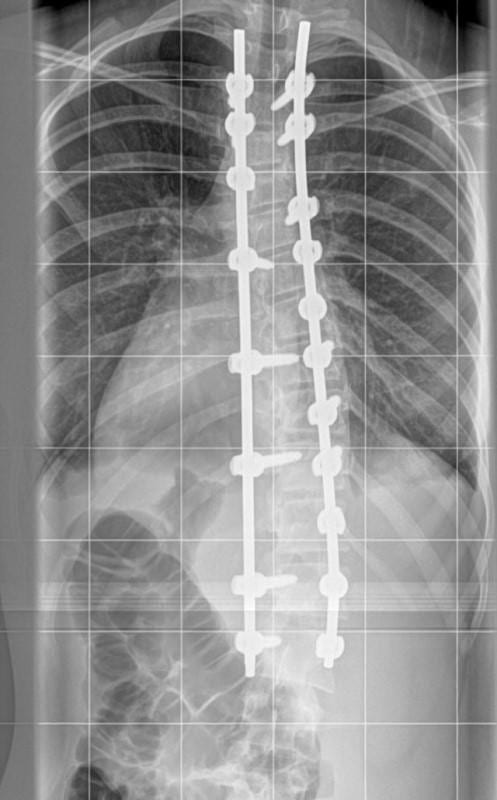

When she was first told about the surgery, Lily didn’t want to have it. The operation was a scary procedure, but the doctors told Lily that the curve in her spine was getting worse.

After being so self-conscious about the condition, eventually Lily agreed to have the surgery, understanding that it could potentially change her life. No one really wants to have surgery if they can avoid it, but for Lily, this had the potential to make a huge difference.